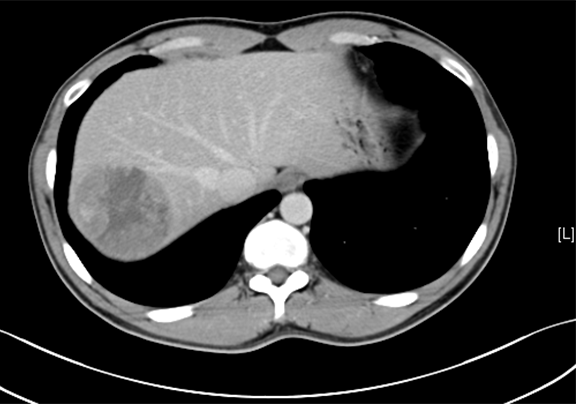

术前CT检查:

动脉期

下腹部增强CT示:肝右后叶占位性病变,考虑肝癌可能性大。